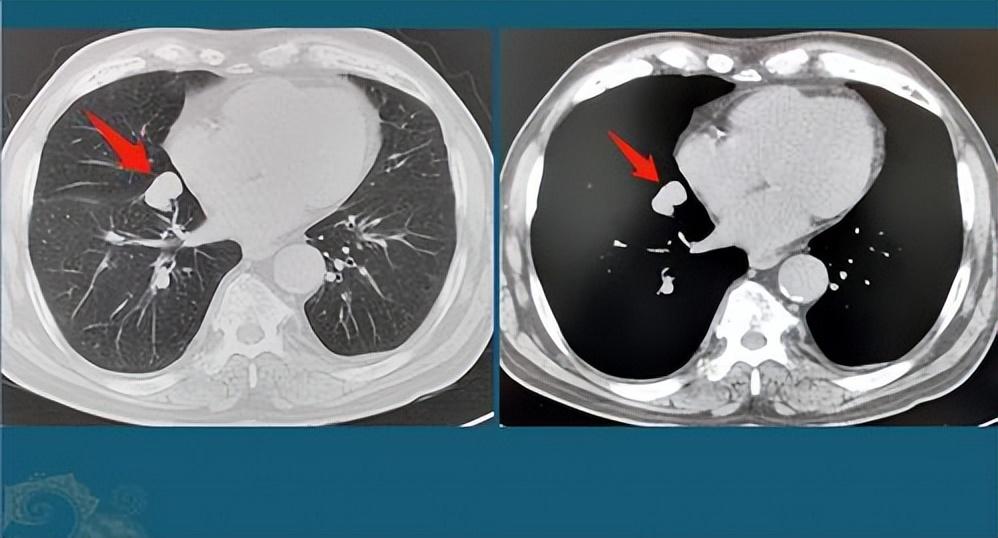

肺結(jié)節(jié)是指肺部出現(xiàn)的直徑小于3厘米的圓形或類圓形病灶,大多數(shù)肺結(jié)節(jié)是良性的,但部分可能需要治療,肺結(jié)節(jié)的癥狀因個(gè)體差異而異,部分患者在早期可能無任何癥狀,因此定期進(jìn)行體檢至關(guān)重要。